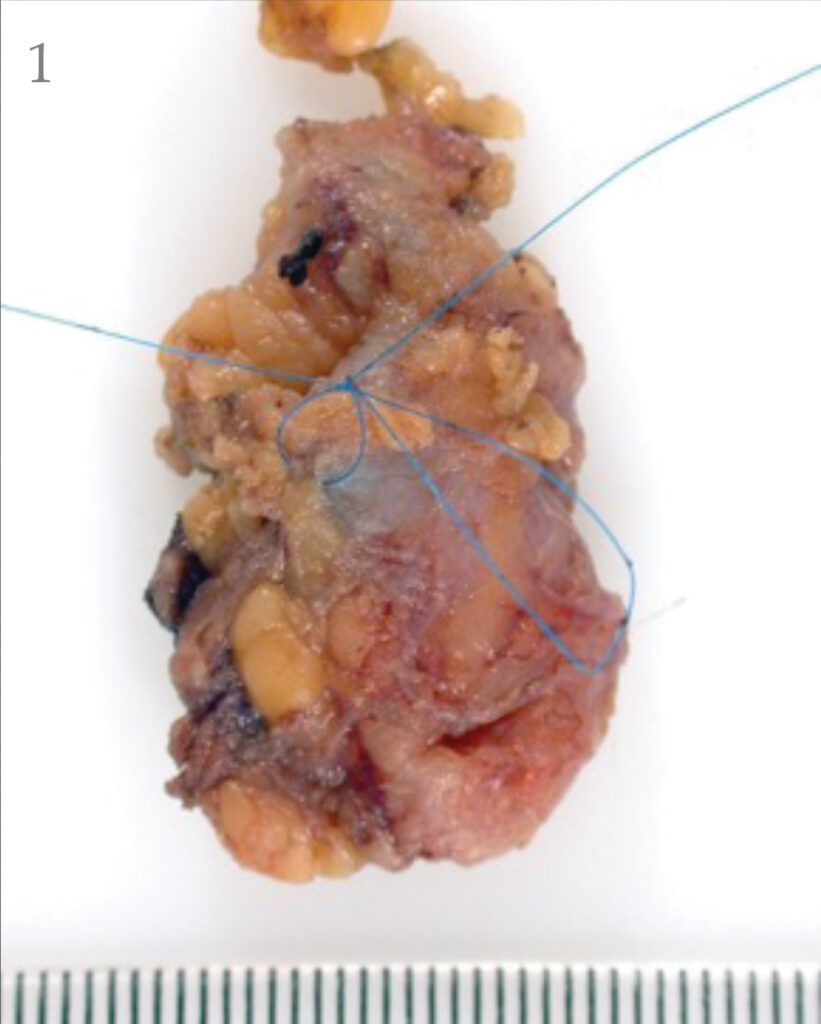

The combination of the radioactive liquid and blue dye is the best way to identify the sentinel node (shown on the next page). The nodes are arranged like a bunch of grapes.

The lymphoscintigraphy and blue dye helps your surgeon to pick out the grape within the bunch, which looks after the part of your body where your melanoma was.

There is a possibility of an allergic reaction to the dye but this is very rare. The surgeon removes that node (or in some cases 2-3 nodes), the operation is usually less than an hour. The pathologist then looks for melanoma cells in the node and the WLE under the microscope.

Pathology of sentinel node biopsy

During the following weeks the pathologist will look carefully at the removed lymph gland and the WLE, under the microscope, for tiny deposits of melanoma. These are often referred to as micro-metastases (see the picture below). Patients normally get the results 3-4 weeks after the surgery.

If a small melanoma deposit (micro metastases ) is detected then the doctor will discuss the options with you. Historically this may have involved removing the remaining nodes. This is known as a lymph gland dissection/completion lymphadenectomy/ lymph node clearance. If micro-metastases are detected (a positive sentinel node biopsy) then the doctor will discuss management of this with you.

If the deposits of melanoma found are larger or there are multiple deposits, they may recommend that the rest of the glands in this area be removed. This is known as a lymph gland dissection/completion lymphadenectomy/lymph node clearance.

- Sentinel node with radioactive hotspot marked.

- Sentinel node with hotspot inked.

- Sentinel node with hotspot ink visible.

- Sentinel node pathology with hotspot ink visible near the melanoma deposit in the node.